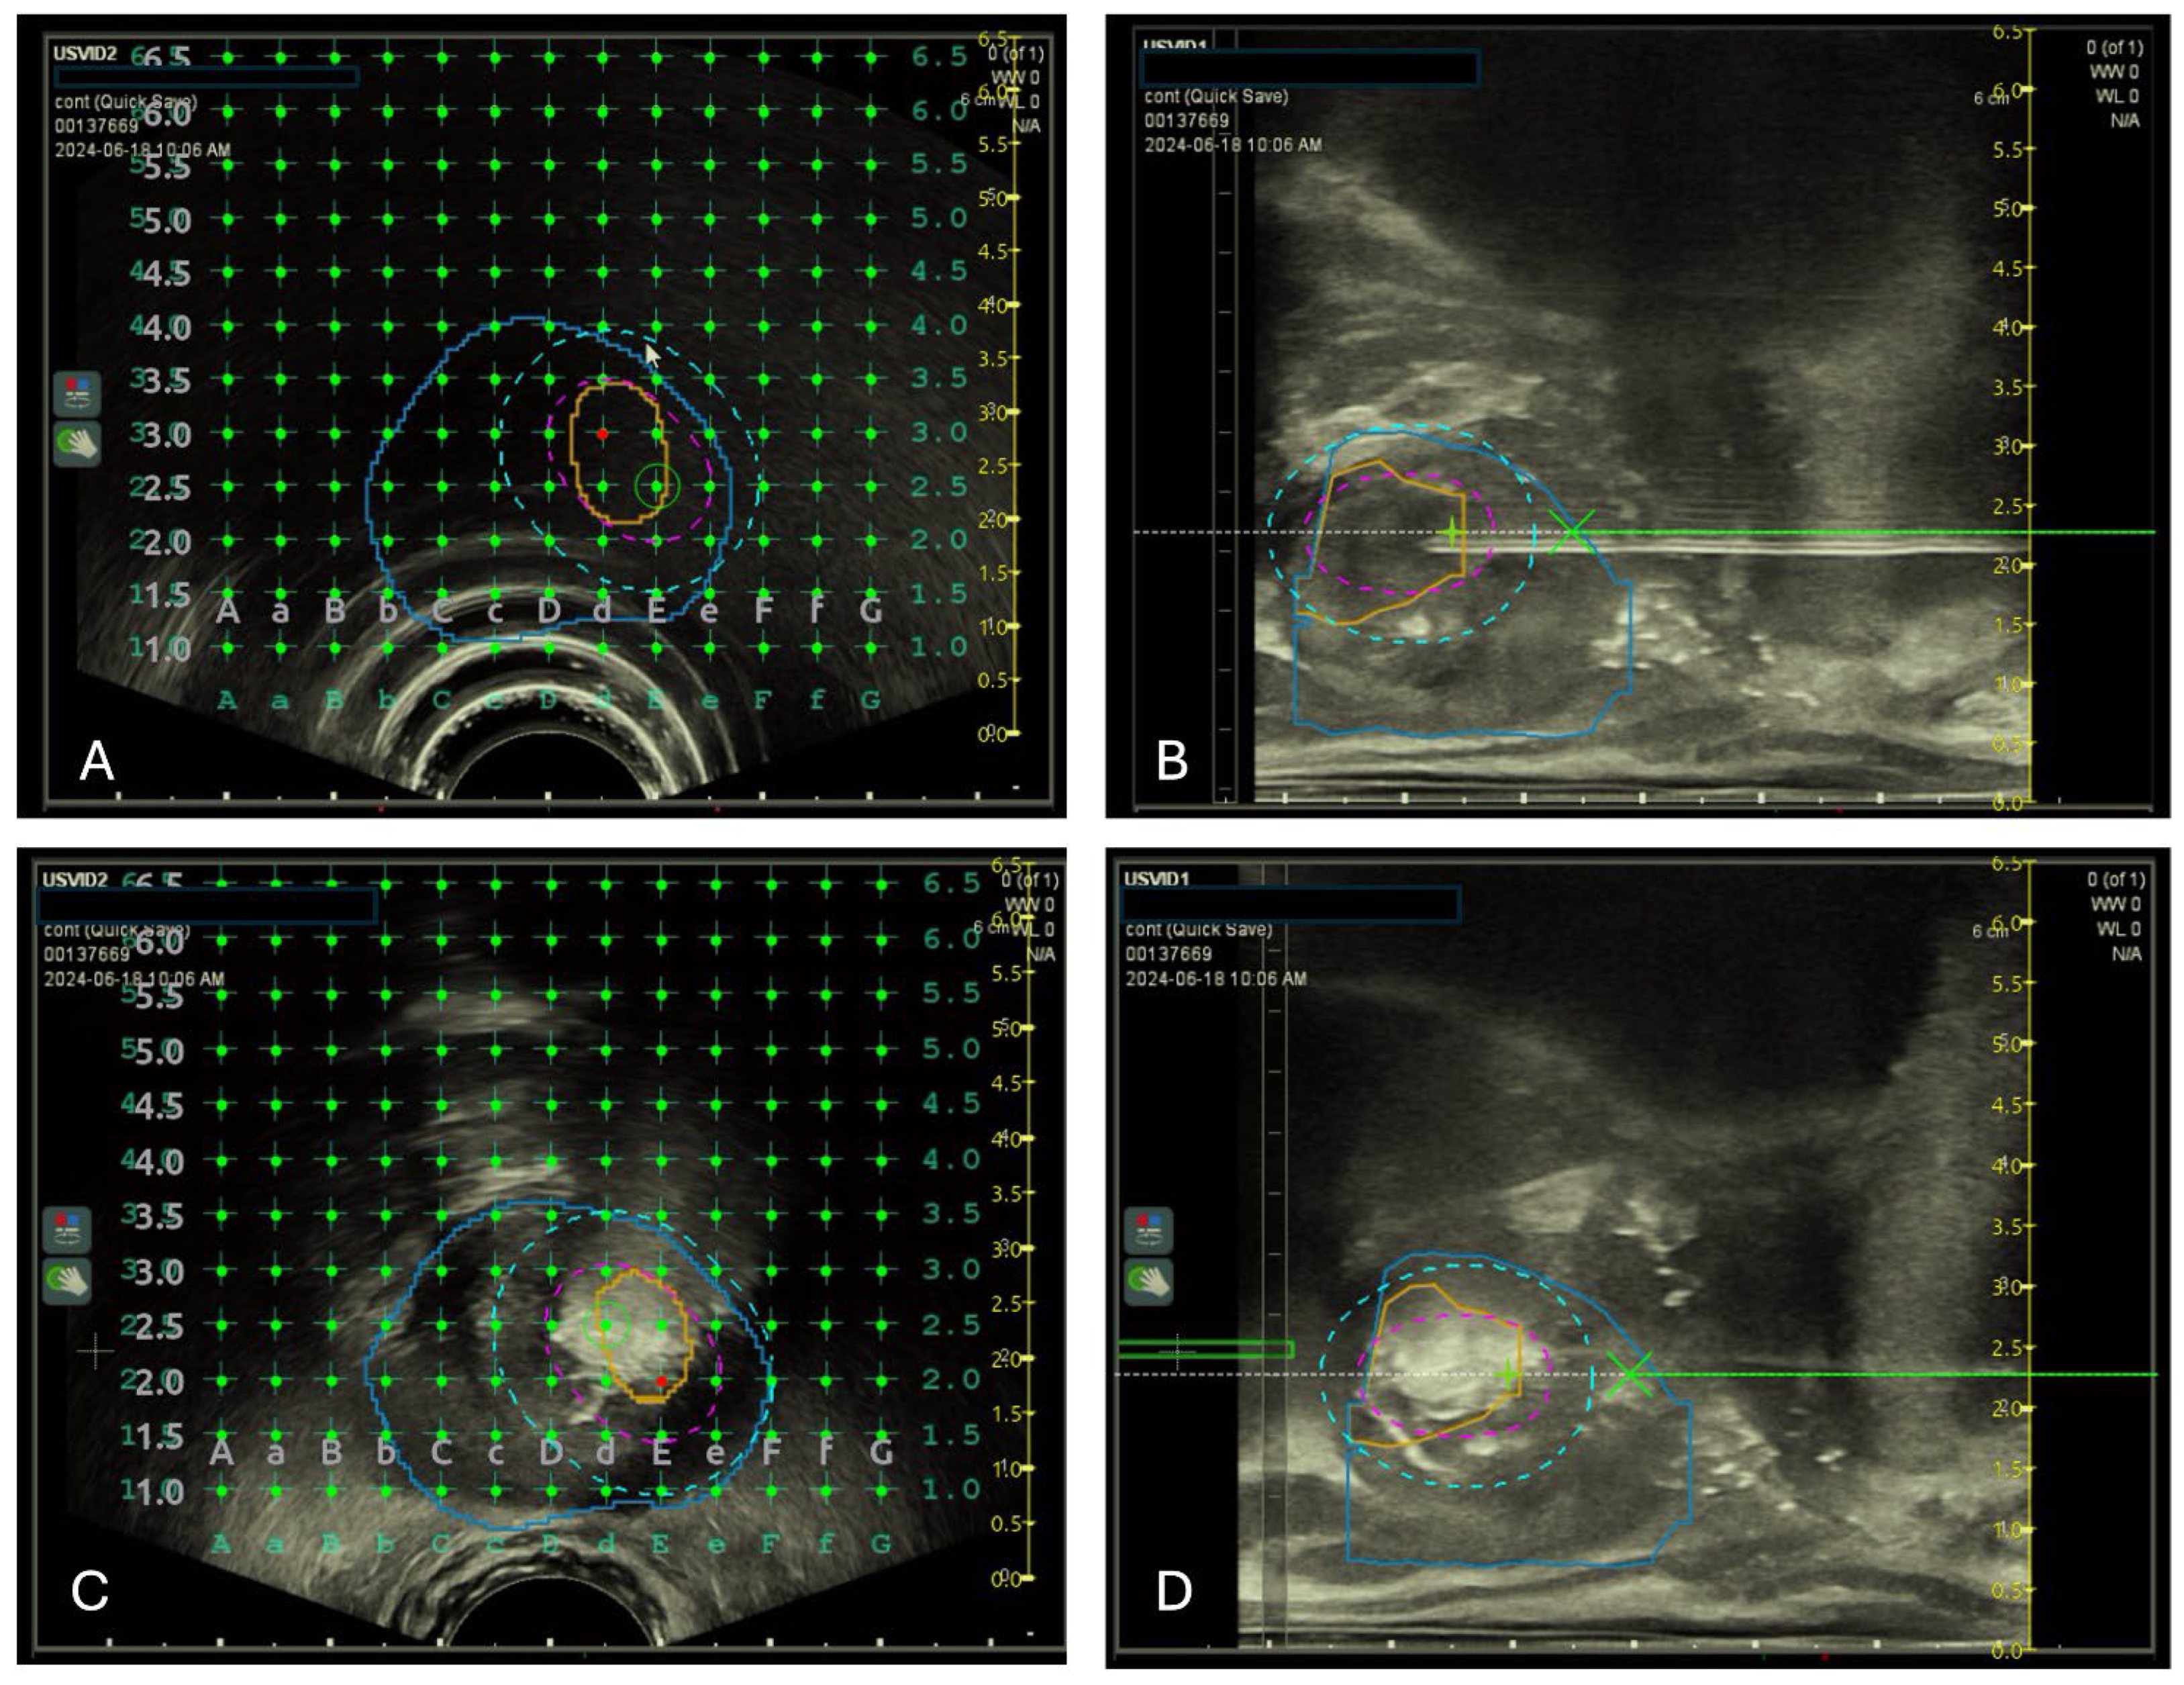

2.4. Focal TPLA Procedure